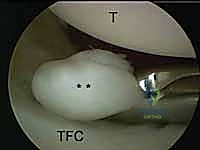

- Function: A crucial viewing portal for the ulnocarpal joint and for introducing instruments to address ulnar-sided pathology, particularly TFCC tears.

3. The 6R Portal (Radial to ECU)

- Location: On the radial side of the extensor carpi ulnaris (ECU) tendon.

- Anatomy: The ECU tendon lies within the sixth dorsal extensor compartment. Identifying the ECU is critical.

- Neurovascular Risks: Generally safe, but care must be taken to avoid the dorsal cutaneous branch of the ulnar nerve, which can course near this area.

- Function: Primarily used for instrumentation, especially when working on the ulnocarpal joint or TFCC. It allows for triangulation with the 4-5 portal.

- Function: Indicated for visualizing and débriding palmar tears of the lunotriquetral ligament (LTIL). It aids in the repair or débridement of dorsally located TFCC tears, especially when triangulation from dorsal portals is difficult. It also assesses the dorsal radioulnar ligament, the ECU subsheath, and the radial TFCC attachment.